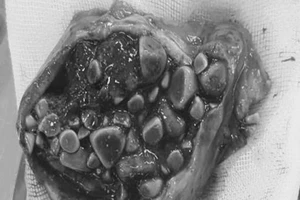

Lấy hàng trăm viên sỏi mật cho nữ bệnh nhân người nước ngoài

Mê ăn thịt mỡ, bà cụ có 806 viên sỏi mật

Kinh hoàng phát hiện 200 viên sỏi trong cơ thể

24/07/2017 12:00